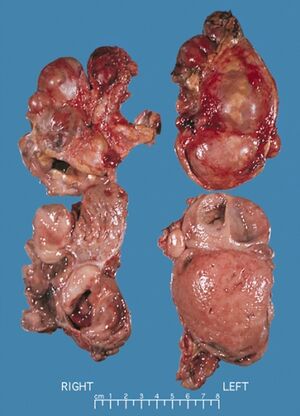

Bilateral pheochromocytomas associated with Multiple endocrine neoplasia type 2 | |

يحدث ورم القواتم في 33-50٪ من حالات الورم الصماوي المتعدد من النوع 2.[3] في الورم الصماوي المتعدد من النوع 2 أ ، يحدث فرط نشاط جارات الدرقية الأولي في 10-50٪ من الحالات وعادة ما يتم تشخيصه بعد العقد الثالث من العمر. نادرًا ما يظهر في الطفولة أو يكون المظهر السريري الوحيد لهذه المتلازمة.[بحاجة لمصدر]يربط الورم الصماوي المتعدد من النوع 2 أ سرطان الغدة الدرقية اللبي بورم القواتم في حوالي 20-50٪ من الحالات وبفرط جارات الدرقية الأولي في 5-20٪ من الحالات.[بحاجة لمصدر] يربط الورم الصماوي المتعدد من النوع 2 ب سرطان الغدة الدرقية اللبي بورم القواتم في 50 ٪ من الحالات ، مع موطن مارفانويد والورم الليفي العصبي المخاطي والهضمي.

في سرطان الغدة الدرقية اللبي العائلي ، لا توجد مكونات أخرى للمرض.[بحاجة لمصدر] في مراجعة لـ 85 مريضًا ، كان لدى 70 مريضًا الورم الصماوي المتعدد من النوع 2 أ و 15 مصابًا بالورم الصماوي المتعدد من النوع 2 ب.[3] كان المظهر الأولي لـالورم الصماوي المتعدد من النوع 2 هو سرطان الغدة الدرقية اللبي في 60 ٪ من المرضى ، وسرطان الغدة الدرقية اللبي المتزامن مع ورم القواتم في 34 ٪ وورم القواتم وحده في 6 ٪. 72 ٪ لديهم ورم القواتم الثنائي